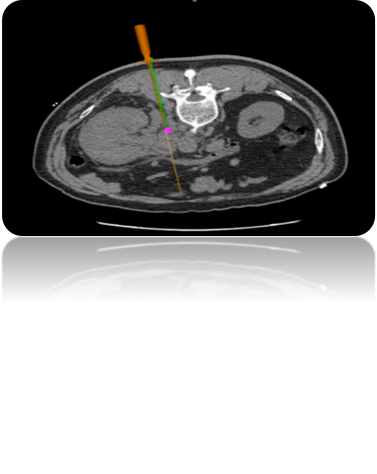

運(yùn)用介入穿刺診療系統(tǒng):通過接受的坐標(biāo)信息與CT圖像融合重建3D模型,幫助醫(yī)生尋找病灶點、提供精準(zhǔn)穿刺路徑規(guī)劃和實時導(dǎo)航;利用磁場發(fā)生器:實時接收來自定位貼片和定位針的信號,反饋到診療系統(tǒng)內(nèi)。

2:路徑規(guī)劃:導(dǎo)入CT圖像后,根據(jù)算法迅速重建3D模型,精準(zhǔn)尋找病灶點及入針點;

4:術(shù)中實時導(dǎo)航:導(dǎo)航針在病人體內(nèi)實時反饋位置,給與醫(yī)生進(jìn)針方向指導(dǎo)。